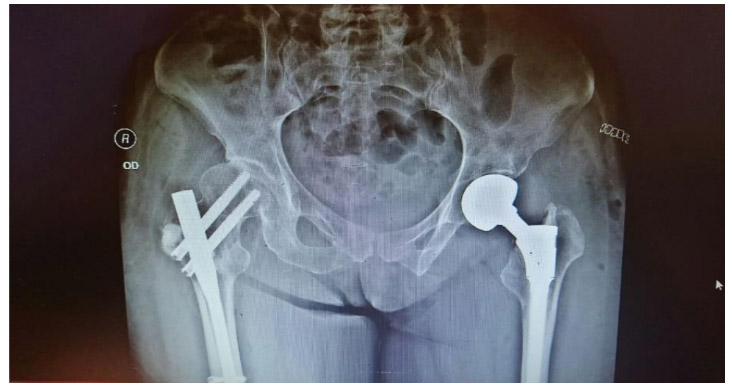

Post-surgery: The X-ray shows cementation and closed pinning after tumor removal on the right side, and partial cementation of the hip prosthesis after removal of the fractured and tumorous bone fragment on the left side.